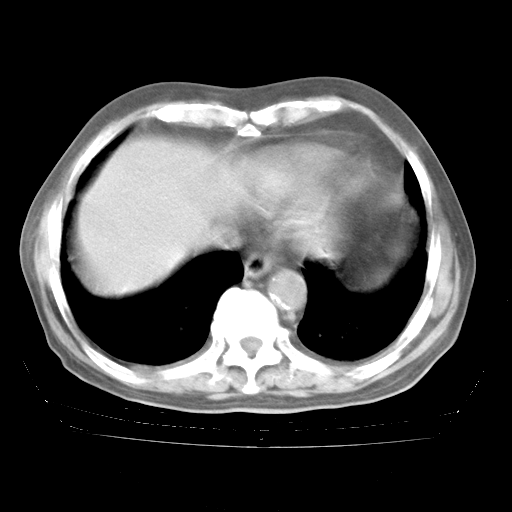

4月28日肺部CT——再次出现类似去年5月9日——透光度降低,“间质性”改变。

4月28日肺部CT——再次出现类似去年5月9日——磨玻璃样、间有“粟粒样”改变。

4月28日肺部CT